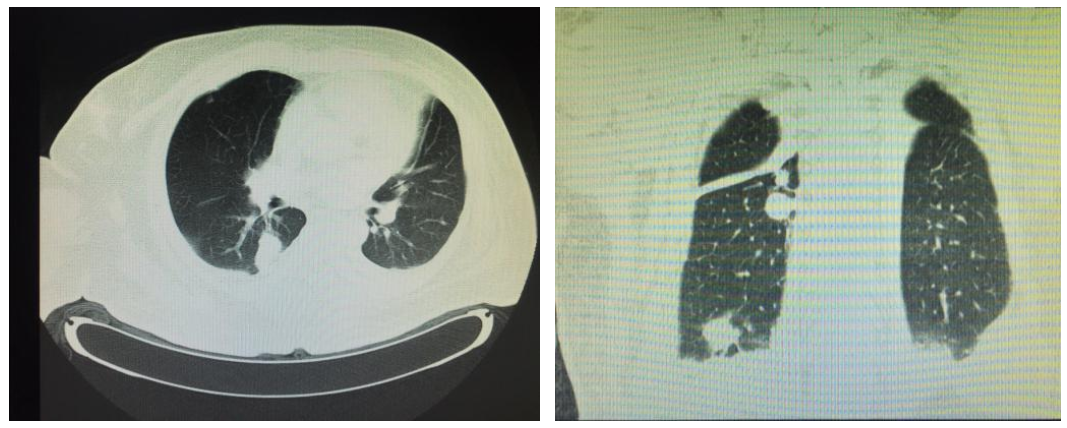

辅助检查:血常规:WBC 9.02×109 /L 、NEUT 7.02×109/L、RBC 3.53×1012/L、Hb 109g/L、PLT 88×109/L;凝血功能:PT 14.7s、PTA 66.9%、INR 1.27;肝脏生化学:TP 62.2g/L、ALB 41g/L、ALT 34 U/L、AST 71U/L、TB 87.9mmol/L、DB 35.5 mmol/L、IB 52.4mmol/L、ALP 145 U/L、GGT 77U/L、K+ 3.59mmol/L、Na+ 134mmol/L、BUN 3.07mmol/L、CREA 53.7μmol/L;血氨:29.5μmol/L。胸部CT:右下肺炎症。

2016.6.16胸部CT:右下肺炎症(无明显呼吸道感染症状、体征)

肺部CT:真菌型肺炎

入院诊断:①肝硬化,②糖尿病,③银屑病,④软组织感染,⑤真菌性肺炎